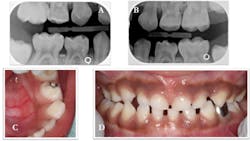

We applied SDF (Advantage Arrest, Elevate Oral Care LLC) and resin-modified glass ionomer (Fuji II LC, GC America Inc.) temporary restorations to the carious lesions on teeth Nos. B and L, and continued to monitor them at three-month intervals. After one year of follow-up, the restorations were intact, and the family had made dramatic improvements in controlling the primary etiologic factor (figure 3). After two years of follow-up, the temporary restoration on tooth No. L fell out and required replacement (figure 4).

Figure 3: SDF plus resin-modified glass ionomer was placed on teeth Nos. B and L using the SMART technique. Restorations were intact 12 months later (tooth No. B shown in photo A, and tooth No. L shown in photo B).

Figure 4: Radiographs at 24 months showed an intact SMART restoration on the occlusal of tooth No. B (photo A) and minimal, if any, progression of the lesion on tooth No. L (photo B). The temporary SMART restoration was missing from the cavitated lesion on tooth No. L (photo C). A stainless-steel crown was placed over tooth No. L using the Hall Technique (photo D).

The lesion was stable and had not progressed, but the cavity served as a food trap. Rather than replace the failed temporary, we recommended placing a definitive restoration—in this case, a stainless-steel crown based on the child’s caries risk. Since the child was still a highly anxious patient, we used the Hall Technique. We applied topical anesthesia to the gingiva, verified the size of the crown, and cemented the crown with glass ionomer cement (Ketac Cem, 3M ESPE). The occlusion was high upon dismissal from the clinic, but it normalized by the time the patient returned for his follow-up visit one month later. This child’s dental disease has been managed very well under the chronic disease-management framework.